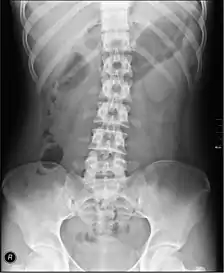

سایر اسکلتهای محوری

ستون فقرات (ستون مهره ای) تصویربرداری رادیوگرافی ستون فقرات یک دوز مؤثر تقریباً 1.5mSv را به وجود میآورد که قابل مقایسه با زمان تابش پس زمینه ۶ ماه است.

- مهرههای کمری: AP و جانبی +/- (L5/S1) در انگلستان، با سطح اریب و خمیدگی و تعمیم، کمیاب (نادر) است. در ایالات متحده آمریکا، تصاویر پایه عبارتند از AP، دو سطح اریب، جانبی و جانبی L5-S1 نقطه ای به منظور تجسم بهتر فضای بین L5-S1. پروجکشنهای ویژه AP عطف راست و چپ و همچنین صفحه جانبی با گسترش و خمیدگی هستند.